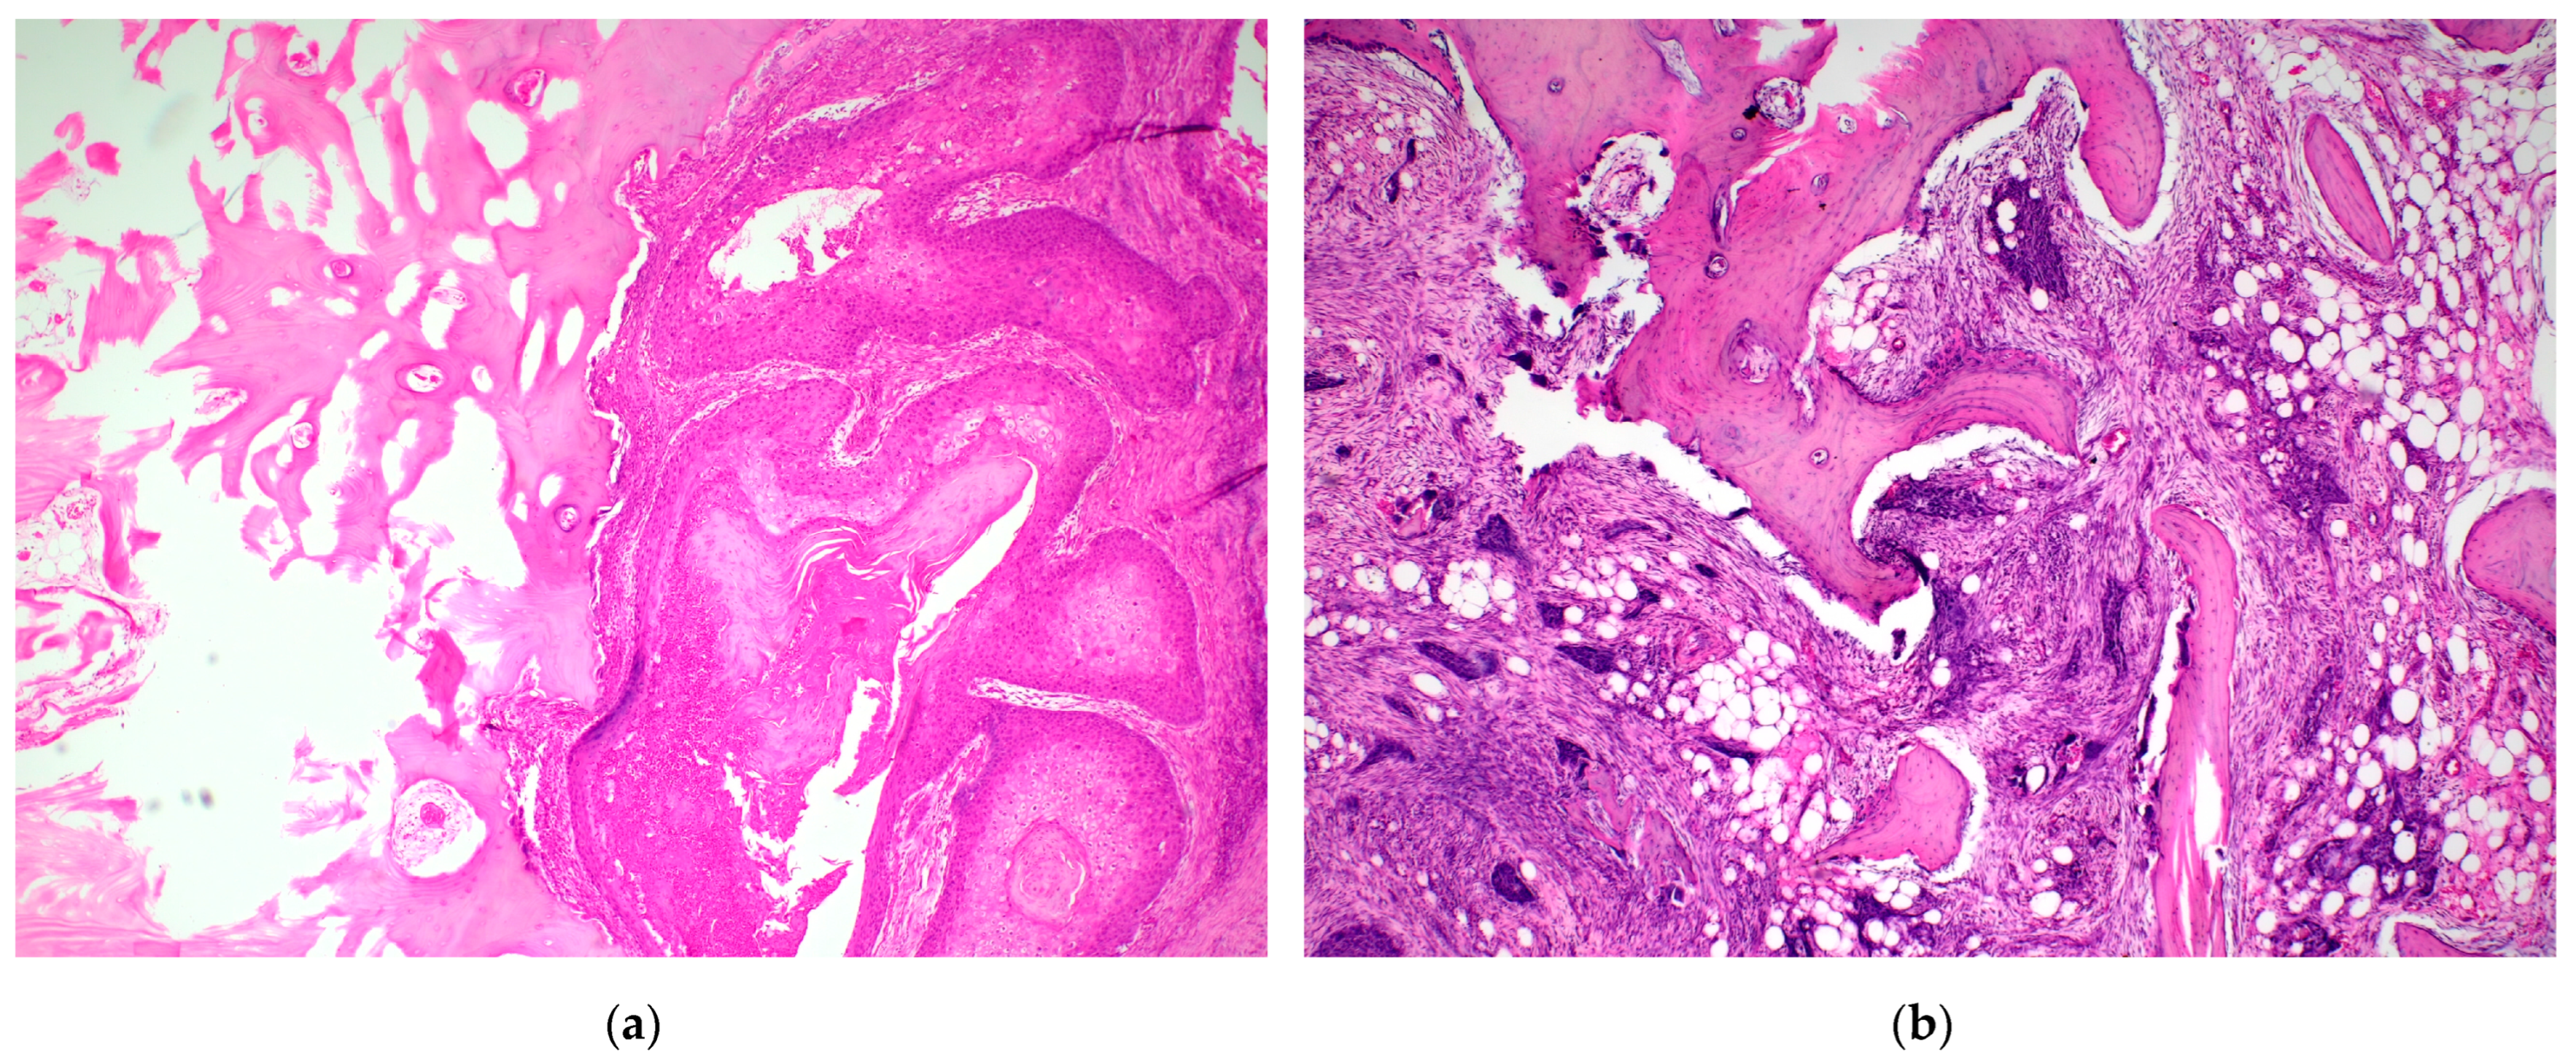

2.2. Histopathological Examination Protocol

- Brown, J.S.; Lowe, D.; Kalavrezos, N.; D’Souza, J.; Magennis, P.; Woolgar, J. Patterns of invasion and routes of tumor entry into the mandible by oral squamous cell carcinoma. Head Neck 2002, 24, 370–383. [Google Scholar] [CrossRef]

- Wong, R.J.; Keel, S.B.; Glynn, R.J.; Varvares, M.A. Histological pattern of mandibular invasion by oral squamous cell carcinoma. Laryngoscope 2000, 110, 65–72. [Google Scholar] [CrossRef]

- Slootweg, P.J.; Müller, H. Mandibular invasion by oral squamous cell carcinoma. J. Cranio-Maxillofac. Surg. 1989, 17, 69–74. [Google Scholar] [CrossRef]